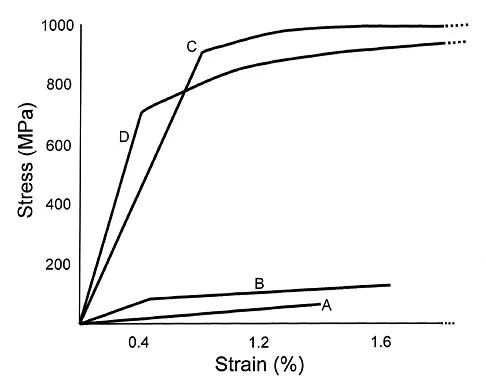

Question 85

Plots of stress versus strain for four orthopaedic biomaterials are shown in Figure 3. Referring to the figure, what is the correct identification of the curves?